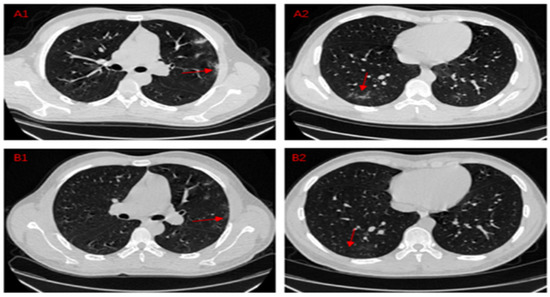

- Meng, H.; Xiong, R.; He, R.; Lin, W.; Hao, B.; Zhang, L.; Lu, Z.; Shen, X.; Fan, T.; Jiang, W.; et al. CT imaging and clinical course of asymptomatic cases with COVID-19 pneumonia at admission in Wuhan, China. J. Infect. 2020, 81, 33–39. [Google Scholar] [CrossRef] [PubMed]